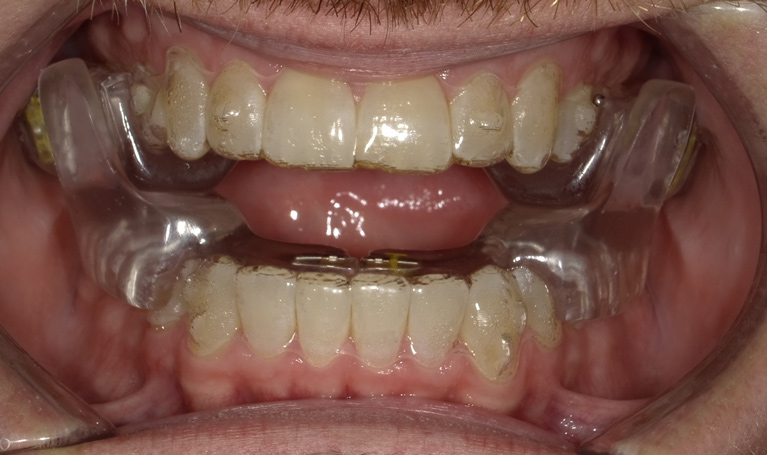

Fig 8. The appliance worn during treatment, anterior view (Fig 8), right side view (Fig 9), left side view (Fig 10), and upper arch view (Fig 11).

Figure 8

Fig 9. The appliance worn during treatment, anterior view (Fig 8), right side view (Fig 9), left side view (Fig 10), and upper arch view (Fig 11).

Figure 9

Fig 10. The appliance worn during treatment, anterior view (Fig 8), right side view (Fig 9), left side view (Fig 10), and upper arch view (Fig 11).

Figure 10

Fig 11. The appliance worn during treatment, anterior view (Fig 8), right side view (Fig 9), left side view (Fig 10), and upper arch view (Fig 11).

Figure 11

Intraoral scans were taken to document the patient's entire palate and bite registration. Scans were sent to the clinical team for the fabrication of a clear aligner/sleep appliance for the patient to wear; the chosen appliance fits over clear aligners, regardless of the tray number the patient may need (Figure 7 through Figure 11).

After the appliance was delivered, additional photographs were taken with the camera to ensure that the appliance was delivered as intended, to document the case, and to show the patient the ideal fit of the appliance in his mouth as instructions were reviewed with him.